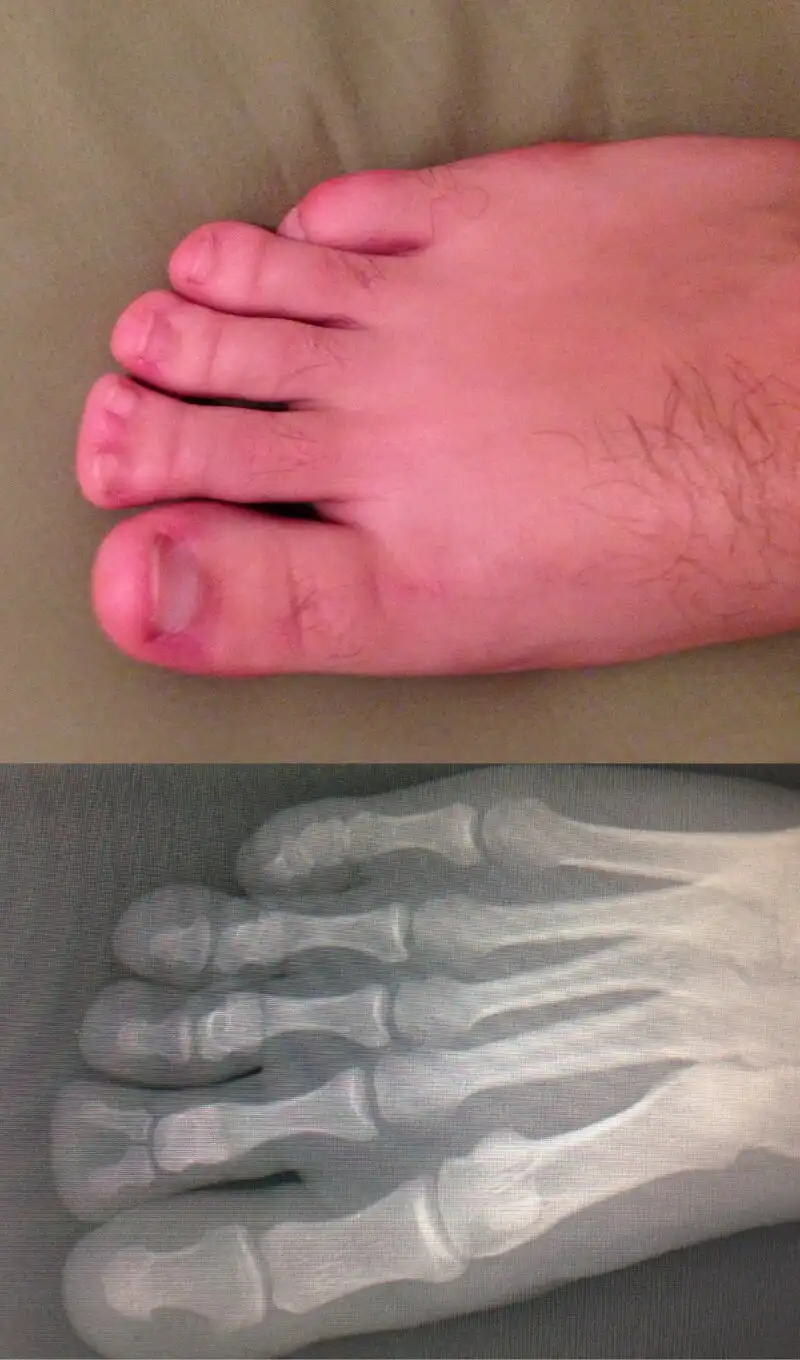

Пациент выслал фото врачу. Тот долго не мог понять, что со стопой

Просто выбирайте нормальный фон!

Девушки и маникюр/педикюр